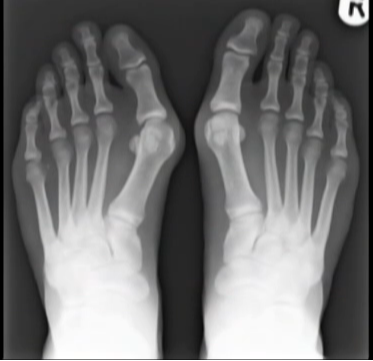

Hình ảnh chụp X-quang xương bàn chân bị tổn thương do đi giày cao gót.

Với sự trợ giúp của máy quét, các chuyên gia tại bệnh viện đã có thể thấy rằng mang chiếc giày cao gót buộc bàn bàn chân phải ép vào một hình dạng không tự nhiên.

Điều này sẽ khiến bàn chân bị đau và tổn thương kéo dài, đặc biệt nếu thường xuyên sử dụng giày cao gót.

Đi giày cao gót khiến đôi chân bạn không được tự do, xương bàn chân bị ép theo khuôn dẫn đến dễ bị dị dạng.